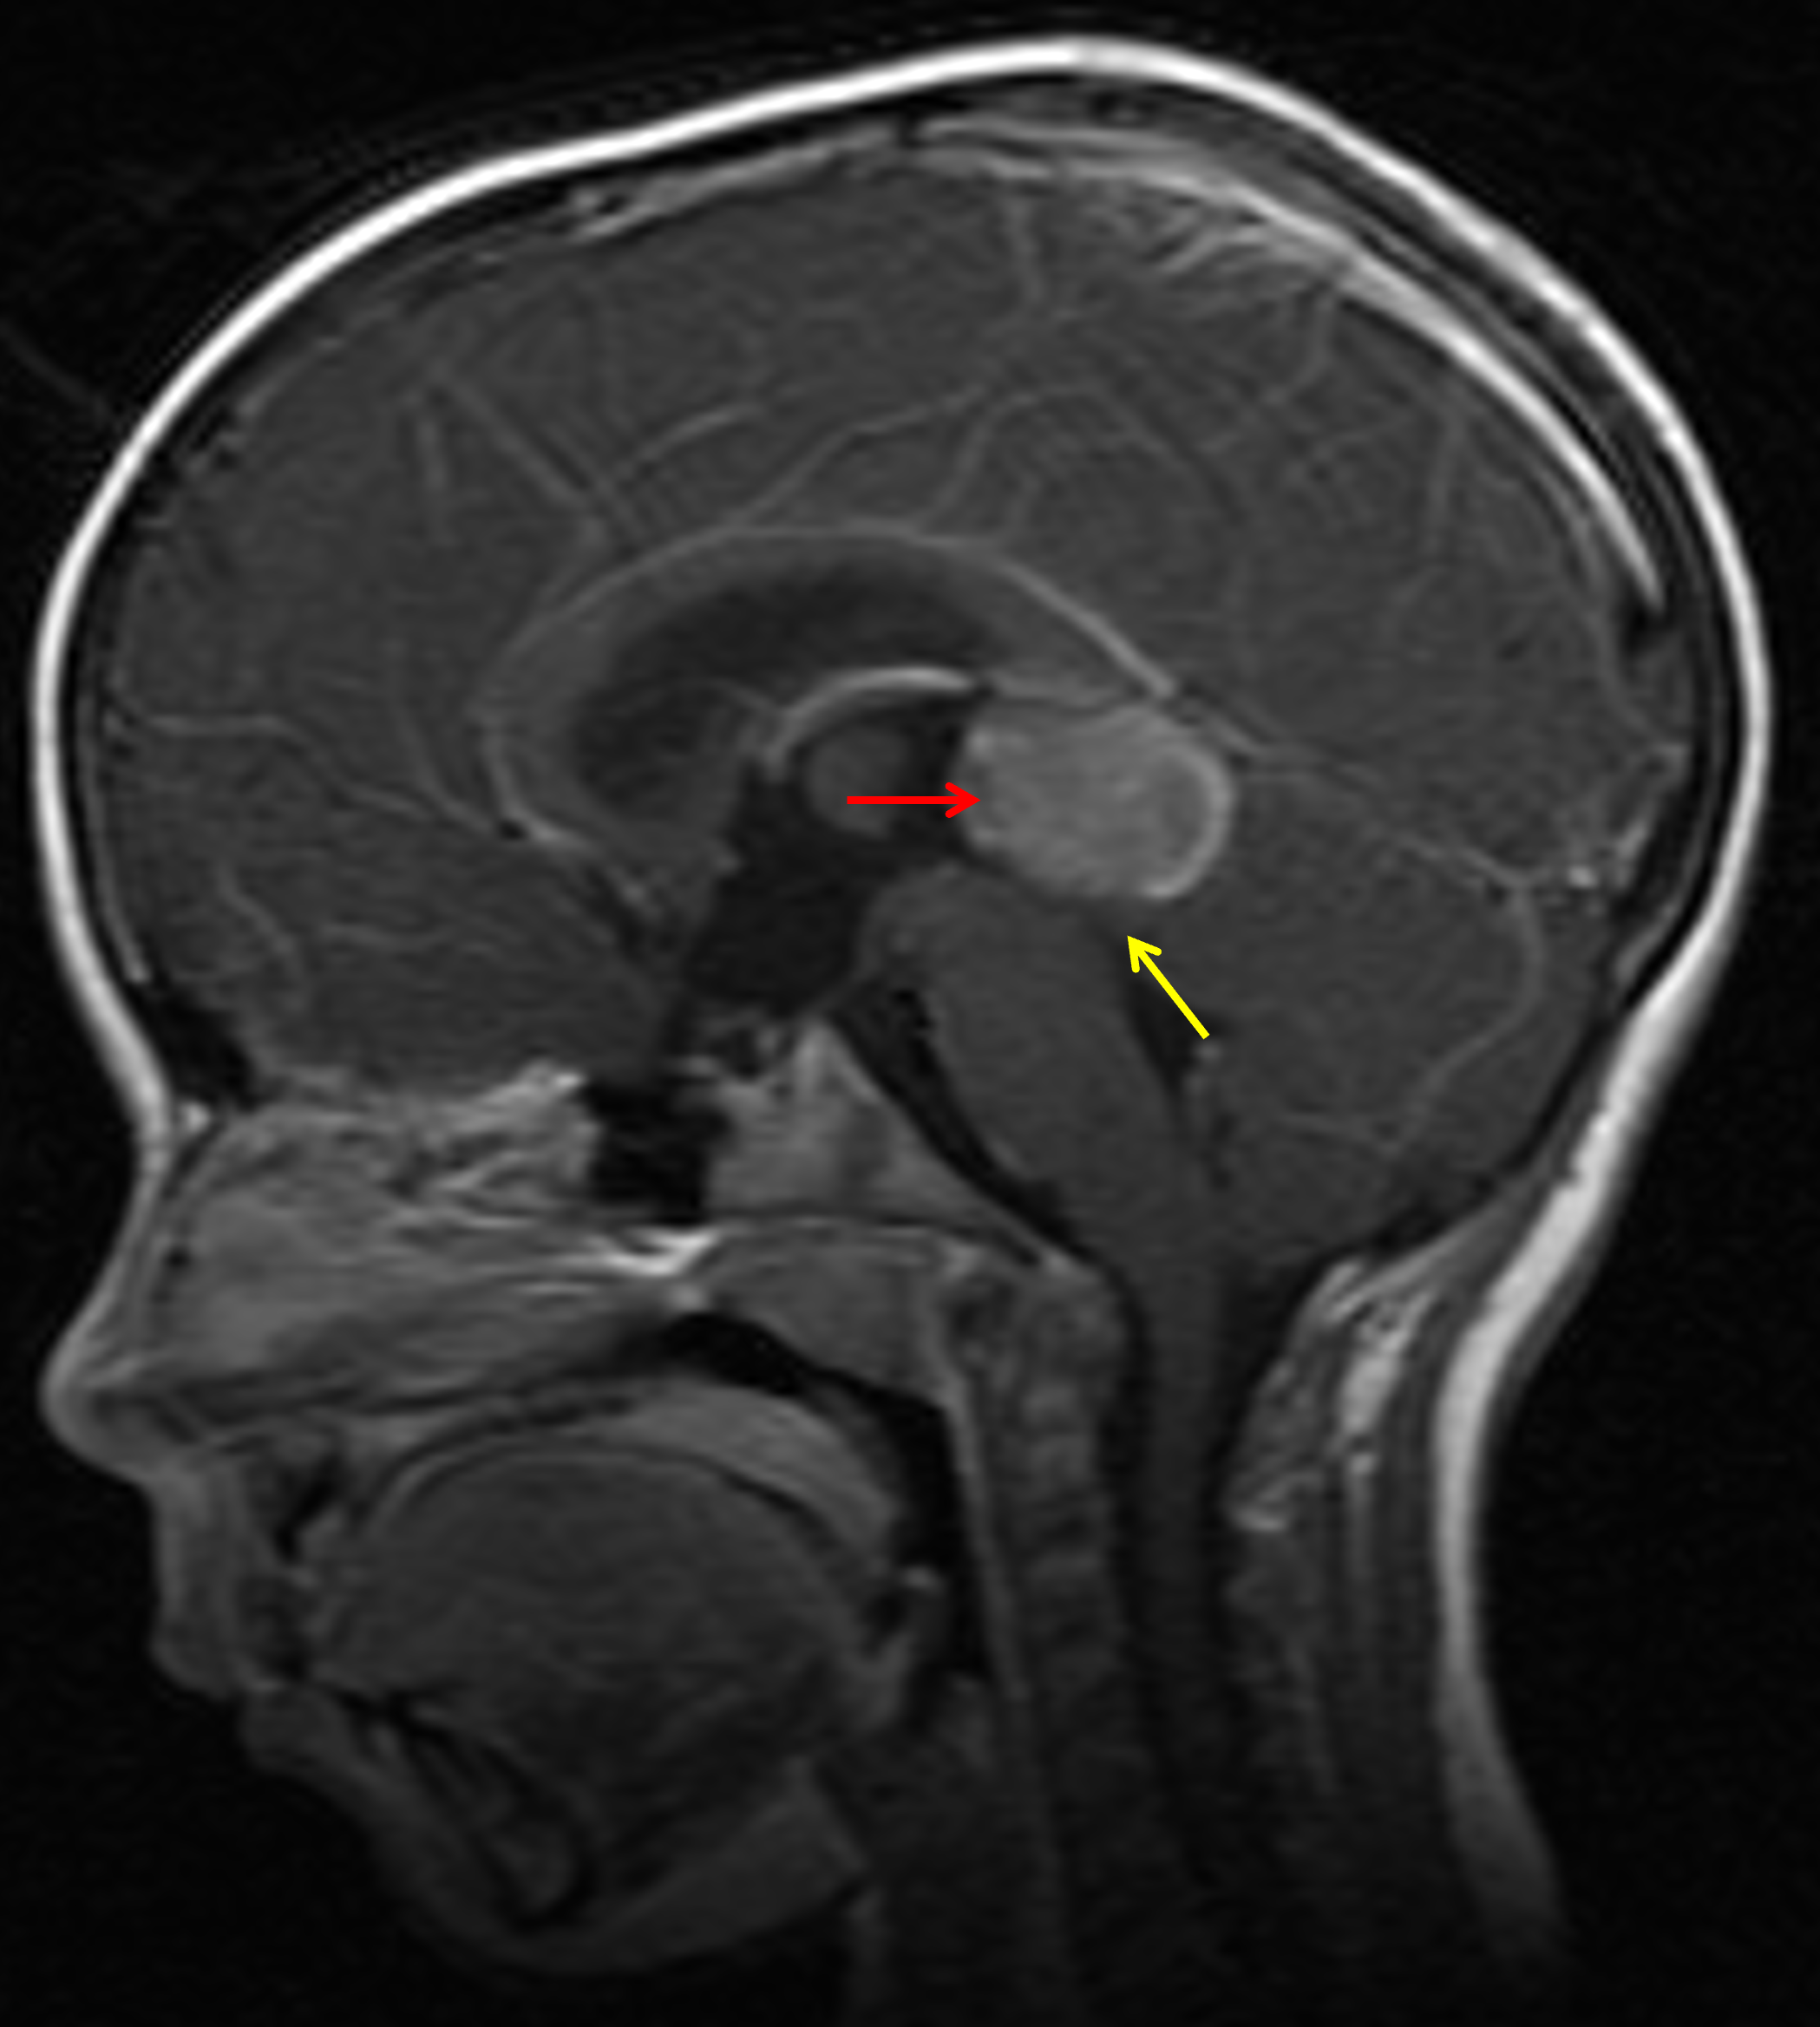

Age: 5

Sex: Female

Indication: Headache, drowsiness

Pineoblastoma